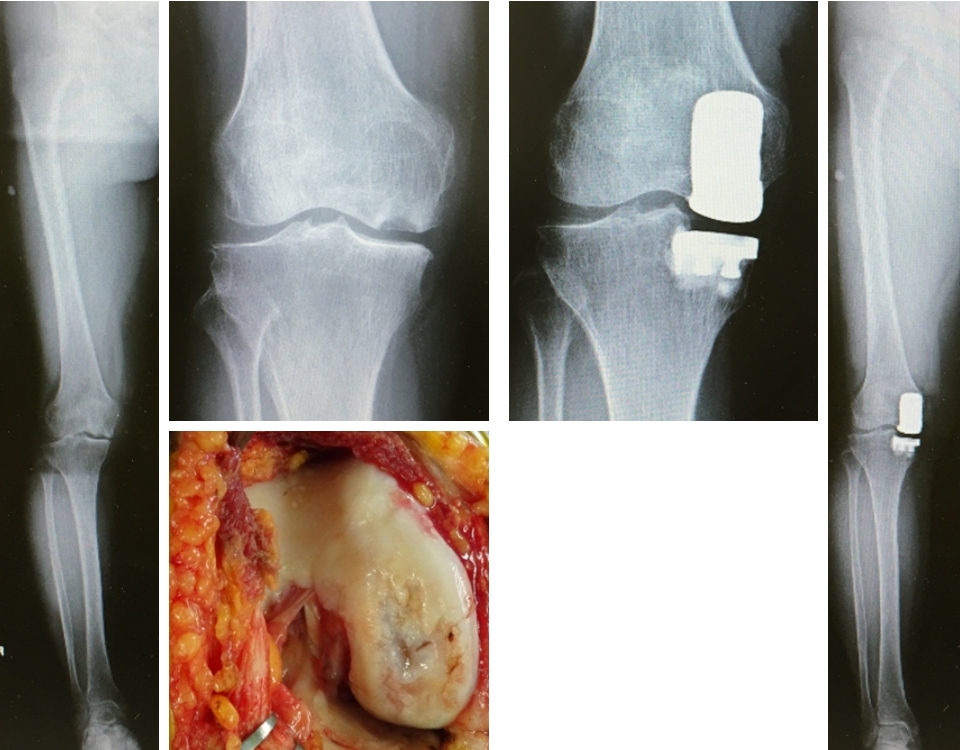

知って得する身体の話 第12回 膝蓋骨高位症 変形性膝関節症 足が長い人の悩み 鶴巻温泉病院 神奈川県